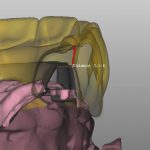

The damage caused by adjusting the zirconia could be very considerable, especially around the access hole since those areas are thinner than the full teeth . For myself i would restore zirconia over metal frame if my choice is hybrid, while removable bar overdenture will be a more predictable and more hygienic choice .